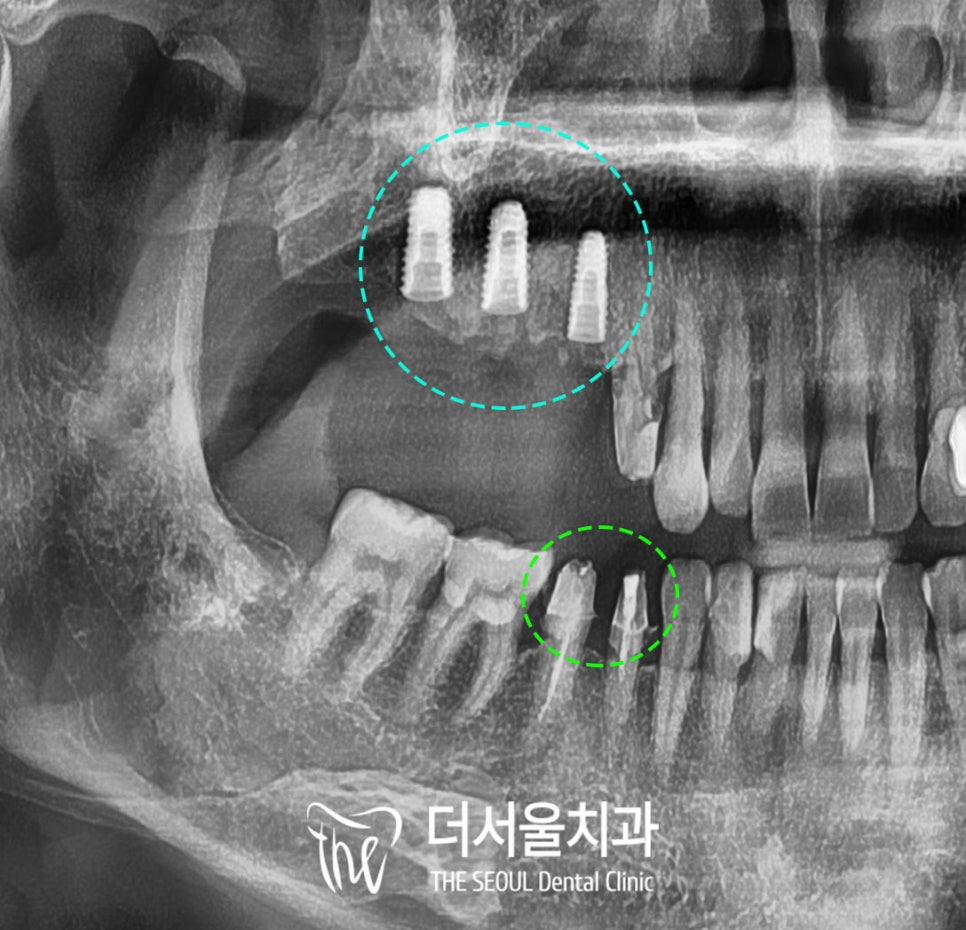

치근단 사진을 찍어서

더욱 자세히 관찰해 보면

이전에 신경치료를 받고

크라운을 씌우지 않은

왼쪽 위 어금니가 잇몸뼈 안쪽에서부터

금이 가고 조금씩 깨지면서

그 주변으로 이물질과 세균이 들어가

뼈가 많이 녹았습니다.

뿌리 끝으로는 염증도 생겨있고

골질도 매우 약해져있는 것이 보이네요.

3차원 CT를 찍어

잇몸뼈 내부를 자세히 관찰해 보니

그간 크라운 보철 없이

어금니 저작력을 하나의 치아가

모두 감당하였기에

이가 상당히 약해져있었습니다.

지속적인 자극과 스트레스로

그 주변 치주 인대와 치조골도

모두 소실되어 있는 상태였죠.